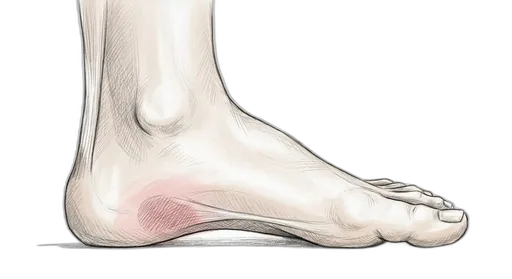

Heel & Arch